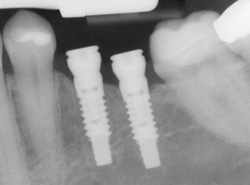

An implant is a synthetic tooth root in the shape of a post that is surgically placed into the jawbone. The implant “root” is usually made of titanium: the same material used in many replacement hips and knees, and a metal that is well-suited to integrating with human bone. After the implant is placed and integrated into the jaw bone, it can be restored with a crown to replace a missing tooth.

Implants can also be used to replace multiple missing teeth (implant bridge) or to secure removable devices such as dentures.